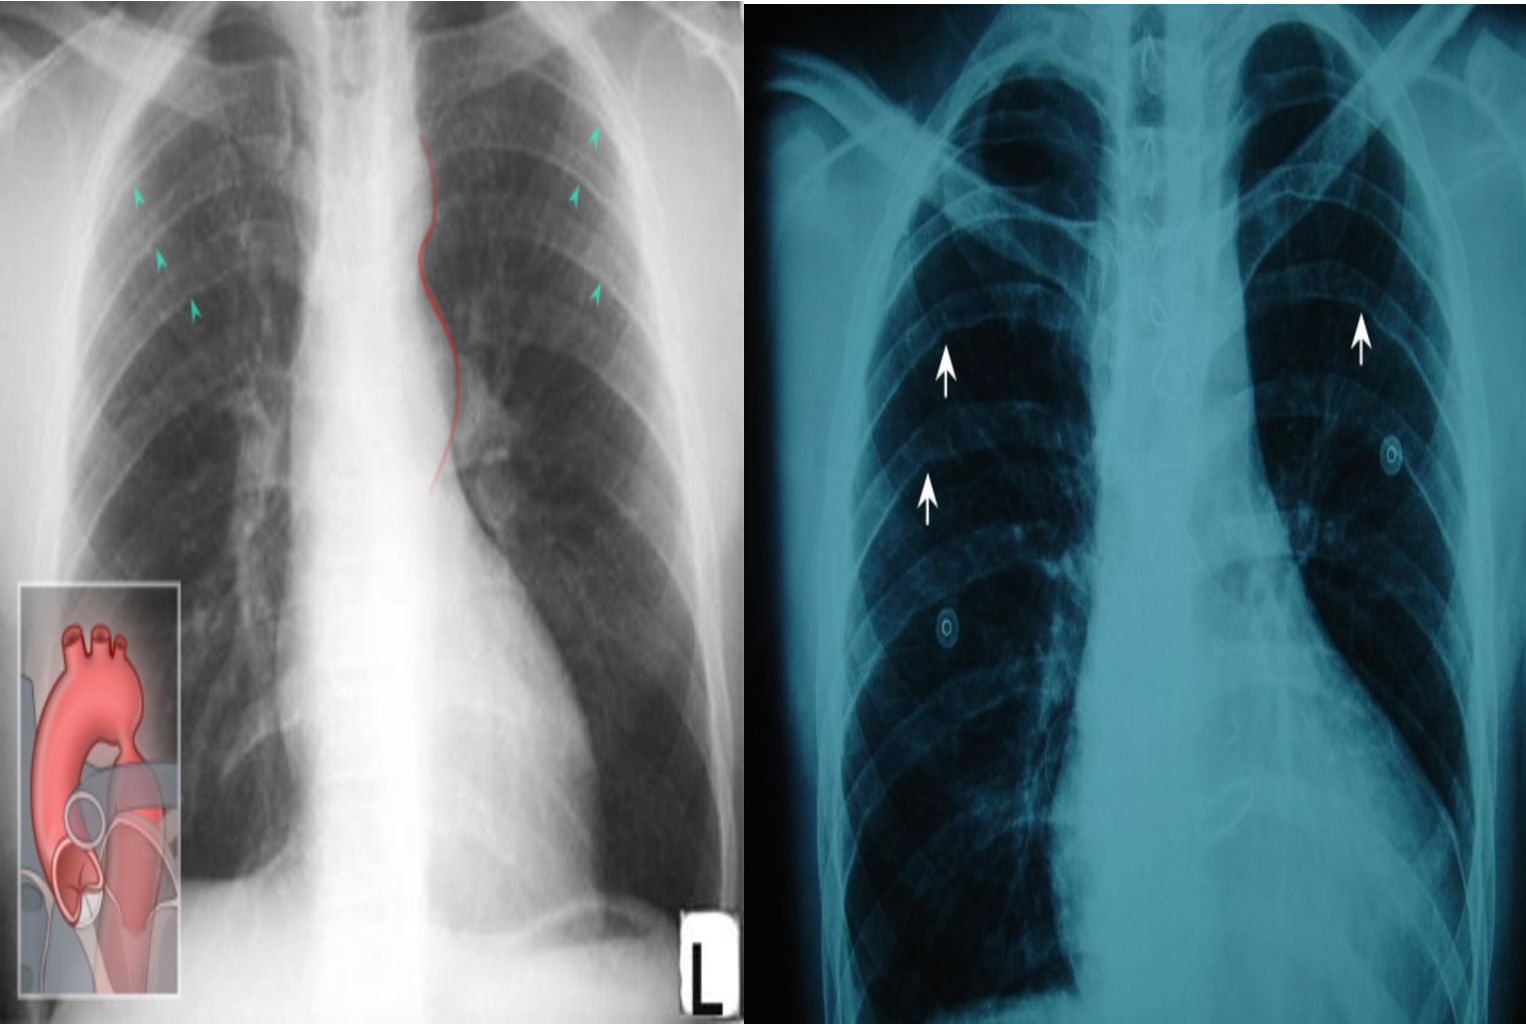

X-ray chest (PA view)

Focal indentation of the distal aortic arch is seen at the location of aortic coarctation (illustration). An additional finding is inferior rib notching (Roesler sign; examples indicated by arrowheads), which is produced by dilated intercostal arteries.

The figure-3 sign of coarctation (indicated by red line) is seen in this patient. It is produced by prestenotic dilatation of the aortic arch and left subclavian artery in combination with post-stenotic dilatation of the descending aorta.

There is mild cardiomegaly with a cardiothoracic ratio >50%, and bilateral rib notching is visible on the inferior border of the ribs (white arrows).

These features indicate coarctation of the aorta.